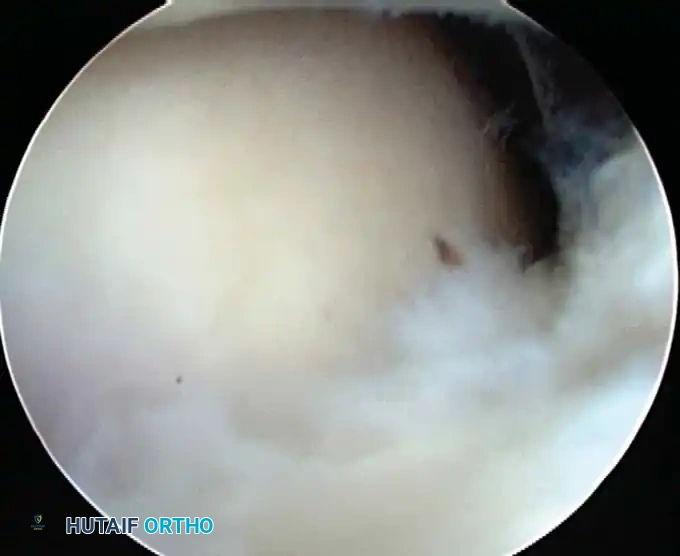

Routine diagnostic arthroscopy is performed using a 4-mm, 30-degree oblique arthroscope. This angle allows for comprehensive visualization of the entire joint through rotation of the lens and manipulation of the arm. In complex instability cases, switching to a 70-degree arthroscope dramatically improves visualization of the anterior glenoid neck and the inferior glenohumeral ligament, which is critical during arthroscopic capsulorrhaphy.

Once diagnostic evaluation is complete and hemostasis is secured, the therapeutic phase commences. Whether performing a SLAP repair, a Bankart stabilization, or a rotator cuff repair, the principles of tissue mobilization, anatomical footprint restoration, and secure biomechanical fixation remain paramount.

Modern arthroscopy relies heavily on suture anchors (biocomposite or all-suture constructs) and advanced arthroscopic knot-tying or knotless techniques. The ability to pass sutures through retracted, fibrotic tissue and secure them under appropriate tension without strangulating the microvascular supply is the hallmark of a master arthroscopist.